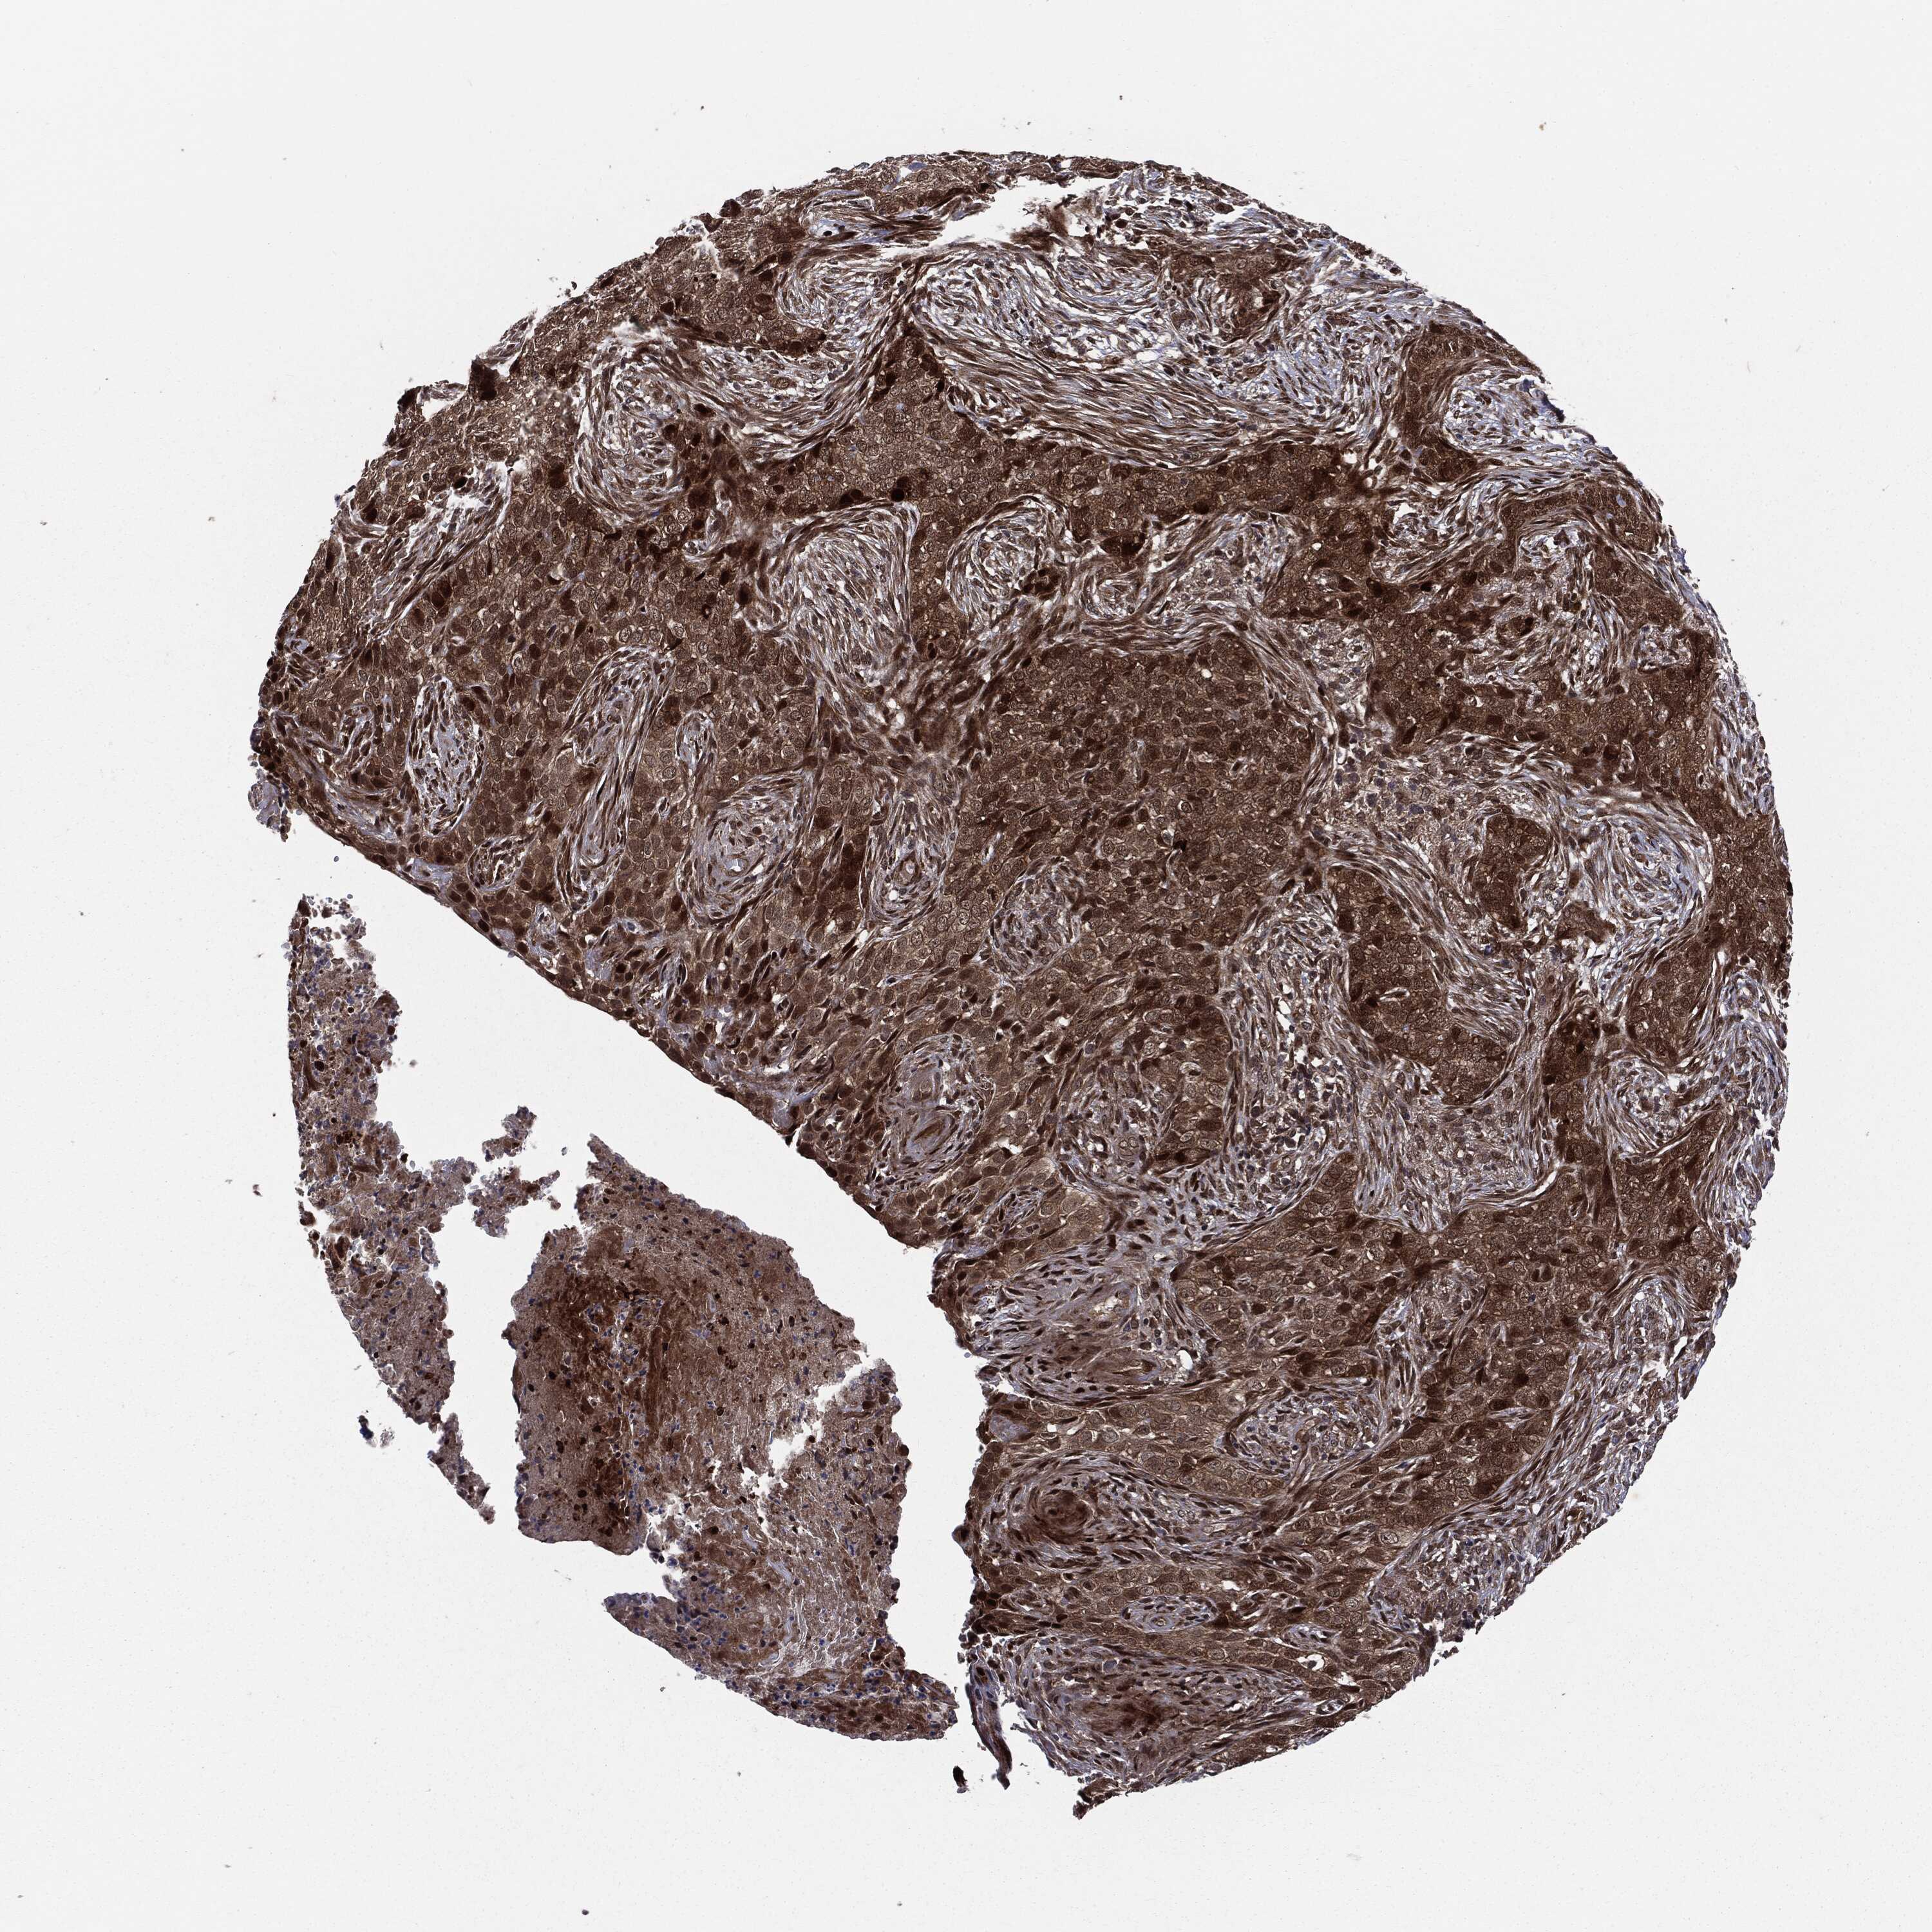

SKIN CANCER - Protein expressioni

A mouse-over function shows sample information and annotation data. Click on an image to view it in a full screen mode. Samples can be filtered based on level of antibody staining by selecting one or several of the following categories: high, medium, low and not detected. The assay and annotation is described here.

Antibody stainingi

Antibody staining in the annotated cell types in the current human tissue is reported as not detected, low, medium, or high, based on conventional immunohistochemistry profiling in selected tissues. This score is based on the combination of the staining intensity and fraction of stained cells.

Each image is clickable and will lead to virtual microscopy that enables deeper exploration of all samples and also displays staining intensity scores, fraction scores and subcellular localization as well as patient and tissue information for each sample.

Antibody CAB080136

Squamous cell carcinoma, NOS

Basal cell carcinoma